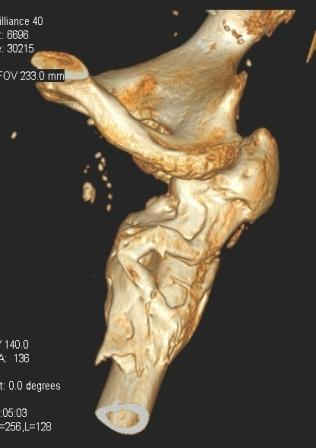

Сросшийся со смещением чрез-подвертельный перелом

Больной Н. 44 года травма 1,5 года назад июнь 2008 года чрез-под вертельный перелом правого бедра. Во время лечения у больного развился алк. делирий, проводилось консервативное лечение перелома.

Осмотрен 30.10.09.

Беспокоят боли, укорочение конечности. Укорочение 3 см. Ногу поднимает, сгибание ограничено, ротационные движения в полном объеме. На КТ перелом сросся за счет костной мозоли. Что делать?

Протез? Если «да» Можно ли обойтись стандартной ножкой Corail?

Или межвертельная остеотомия?